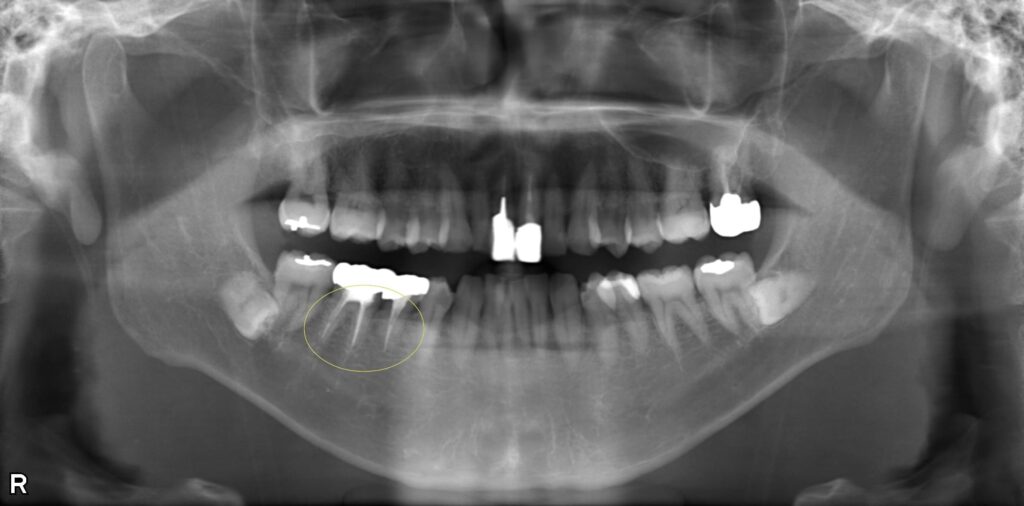

歯髄炎に対する抜髄・根管充填処置の症例

右下の痛みを訴えて来院されました。右下5番・6番に大きな虫歯ができており、歯の神経に炎症を引き起こしている「歯髄炎」という状態でした。 歯髄炎の場合は、炎症が根管内のどの部位まで進行しているかを診断します。 今回のケースでは、根の先まで炎症が進行しておらず、まだ感染を起こしていない状態でしたので、抜髄処置と同時に緊密な根管充填を行いました。 充填処置を即日に行うことで、感染にさらされる機会を最小限に抑えることができます。 術後の経過は良好で、根尖部に透過像もなく安定しています。

症例画像